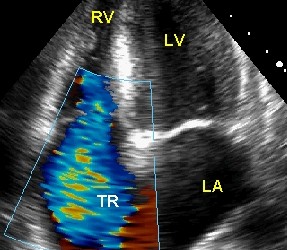

Insuficienţa tricuspidiană

Reprezint? închiderea incomplet? a orificiului tricuspidian în timpul sistolei, stuff sickness permi?ând refluarea sângelui din ventriculul drept în atriul drept.

În timpul contracţiei ventriculului drept, sângele refluează în atriul drept, determinând o creşterea a presiunii în această cameră. Iniţial, prin mecanismele de compensare reprezentate de dilataţia şi hipertrofia atriului drept, debitul cardiac este menţinut la valori normale. Ulterior, se produce decompensarea, cu apariţia stazei venoase sistemice şi a semnelor clinice: turgescenţă jugulară, stază hepatică, edeme periferice, ascită. Unda de refluarea sistolică se transmite în sistemul venos producând pulsul sistolic jugular şi hepatic.

La examenul cordului, auscultator se constată un suflu sistolic de regurgitare tricuspidiană, cu intensitatea maximă parasternal stâng, în spaţiile intercostale 4-5. Suflul este intens, uneori mai accentuat în protosistolă sau, mai rar, în mezo sau telesistolă. Poate iradia către apendicele xifoid, marginea dreaptă a sternului sau apex. Timbrul este asemănător unei „ţâşnituri de aburi”. Suflul se accentuează în inspir (manevra Rivero-Carvalho) sau în timpul manevrei Valsalva.